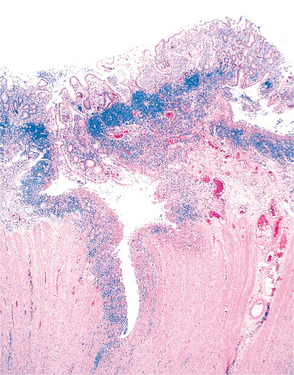

The lesions are granulomatous (epithelioid cells rimmed by lymphocytes) with projections of inflamed tissue surrounded by fibrous scarring narrowing the intestinal lumen (Fig. 16-10). A combination of the granulomas (nodular swelling), ulceration, and fibrosis results in a cobblestone appearance of the mucosal surface of the colon (Fig. 16-11).

Figure 16-10 Crohn’s disease of the colon. A deep fissure extending into the muscle wall and a second, shallow ulcer (upper right). Abundant lymphocyte aggregates are present, evident as blue patches of cells at the interface between the mucosa and submucosa. (From Kumar V: Robbins and Cotran: pathologic basis of disease, ed 7, Philadelphia, 2007, Saunders.)